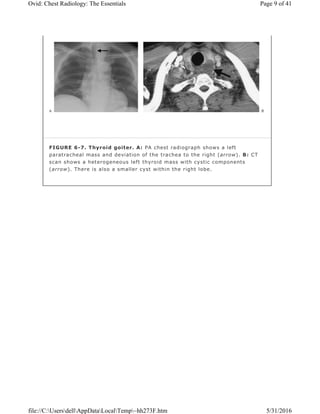

FIGURE 6-7. Thyroid goiter. A: PA chest radiograph shows a left

(arrow). There is also a smaller cyst within the right lobe.

An intrathoracic thyroid mass is usually a benign multi-nodular goiter that

radiography. Many thyroid masses displace or narrow the trachea (Fig. 6-7).